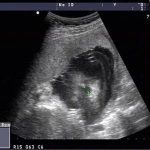

全景顾名思义,扫描范围大,立体成像。能立体成像宫腔,对宫腔畸形的诊断有意义;精确测量骨盆各经线,对预估头盆比值有意义;胎儿立体成像,对发现隐性畸形有意义;对肿瘤立体成像对确定是血供有意义;能显示子宫附件血管影像,对发现子宫和卵巢性流产和不孕有意义。

常规的四维超声扫查视野有限,在遇到较大范围的病变时,有限的超声扫查视野使检查者不能充分掌握病变的范围以及与邻近结构的位置关系,从而影响对病变的准确分析。全景四维彩超可以显示大范围,大病灶等整体解剖结构,便于观察、诊断、存储及测量。其呈像也更真实、不扭曲、不变形。